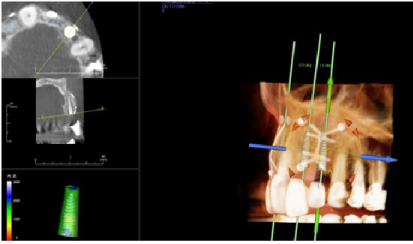

Four months later a new CBCT of the maxillary arch was completed and at all sites, #s 7. 9, and 10 with successful GBR achieved and implant placement was planned using the Anatomage (San Jose, CA, USA) implant planning software (Figures 17, Figure 18, and Figure 19). Each site went from less than 2 mm of width preoperatively to a width of 7 mm four month after grafting.

Figure 17: Post-op four months grafting #7 site CBCT and Anatomage implant planned. Notice the increased bone width from a preoperative width of less than 2 mm to a width greater than 6 mm. View Figure 17

Figure 18: Post-op four months grafting #9 site CBCT and Anatomage implant planned. Notice the increased bone width from less than 2 mm to 7 mm. View Figure 18

Figure 19:Post-op four months grafting #10 site CBCT and Anatomage implant planned. Notice the increased bone width from a preoperative width of less than 2 mm to a width after 4 months of 7 mm. View Figure 19